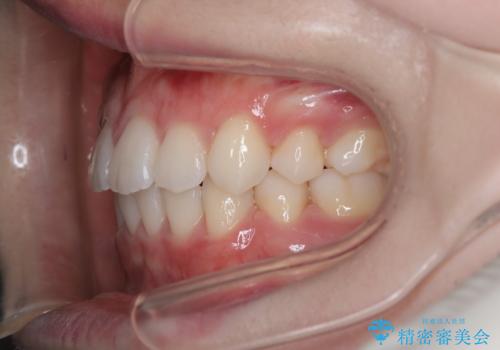

【審美装置】歯を抜いてEラインをきれいに

- 出っ歯を主訴に来院されました。今回は4番の歯を4本抜歯をし、ワイヤー矯正にて治療しました。

抜歯矯正のため2年を予定してましたが、予定よりも早く終わることができました。また口元も下がり、かみ合わせも改善しました。